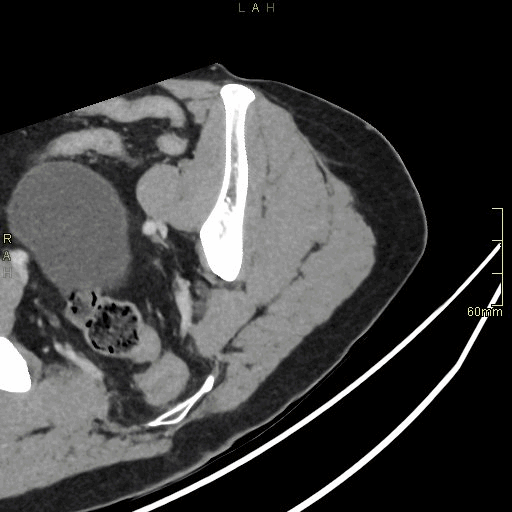

CT Hip Contrast- Soft tissue window (axial)

CT Hip Non Contrast- Soft tissue window (axial)